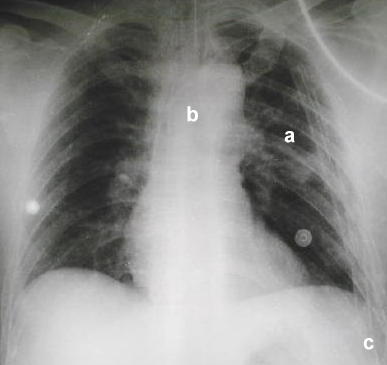

Rx. control

pos - operatorio

Rx. pos - operatoria

inmediata.

a. observe

la expansión pulmonar del lado izquierdo.

b. la

traquea intubada y el mediastino se encuentran centrados en el tórax.

c. dos

tubos torácicos fueron utilizados para drenaje y expansión

pulmonar.

Nota: las imágenes

redondeadas corresponden a electrodos electrocardiográficos.